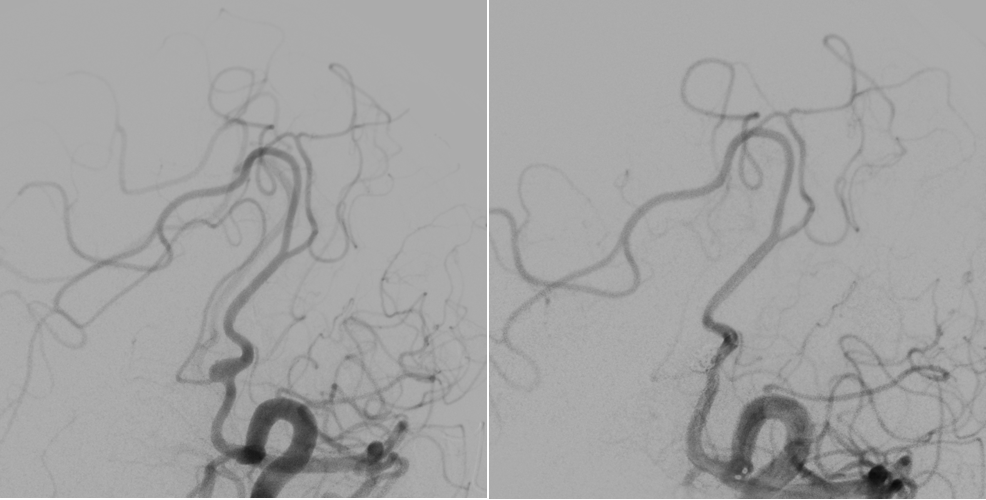

在手术团队的齐心协作下,支架精准释放、随即对动脉瘤进行栓塞。经过3个小时的奋战,即刻造影显示支架内血流通畅,邻近血管未受影响,动脉瘤栓塞满意,手术圆满成功。李女士术后没有任何神经功能受损症状,现已顺利出院。

手术前后造影对比图。